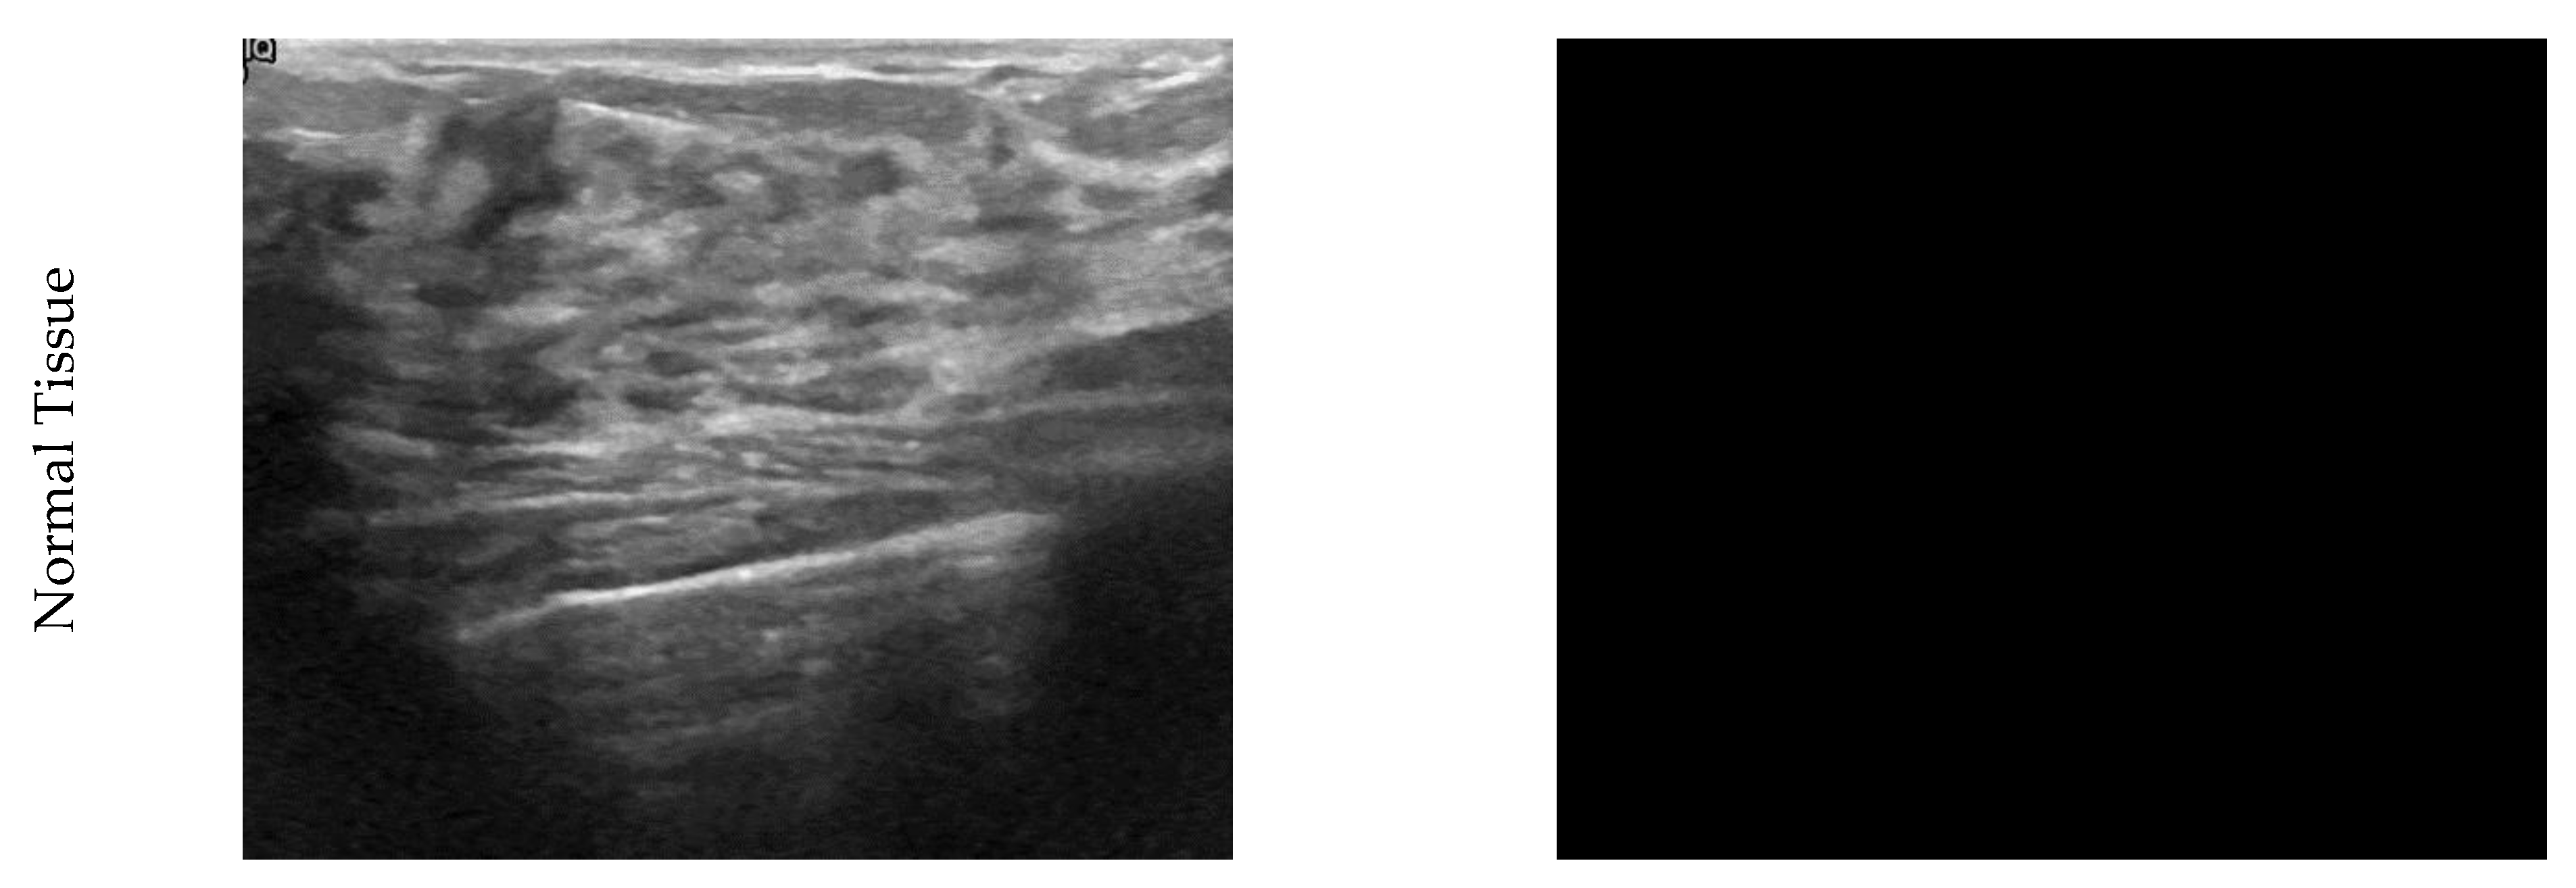

In this paper, segmentation of images has been used to find the primary location of the tumor. Segmentation is not one of the main steps of the convolution and DL algorithm. It has been used to validate the results. By separating pixels with zero values as the background, each non-zero pixel is the mass breast threshold (225). Each remaining pixel is 127 to the normal breast tissue, as shown in Figure 1.

Ultrasound and clustered images of breast cancer for benign, malignant, and normal tissue conditions.